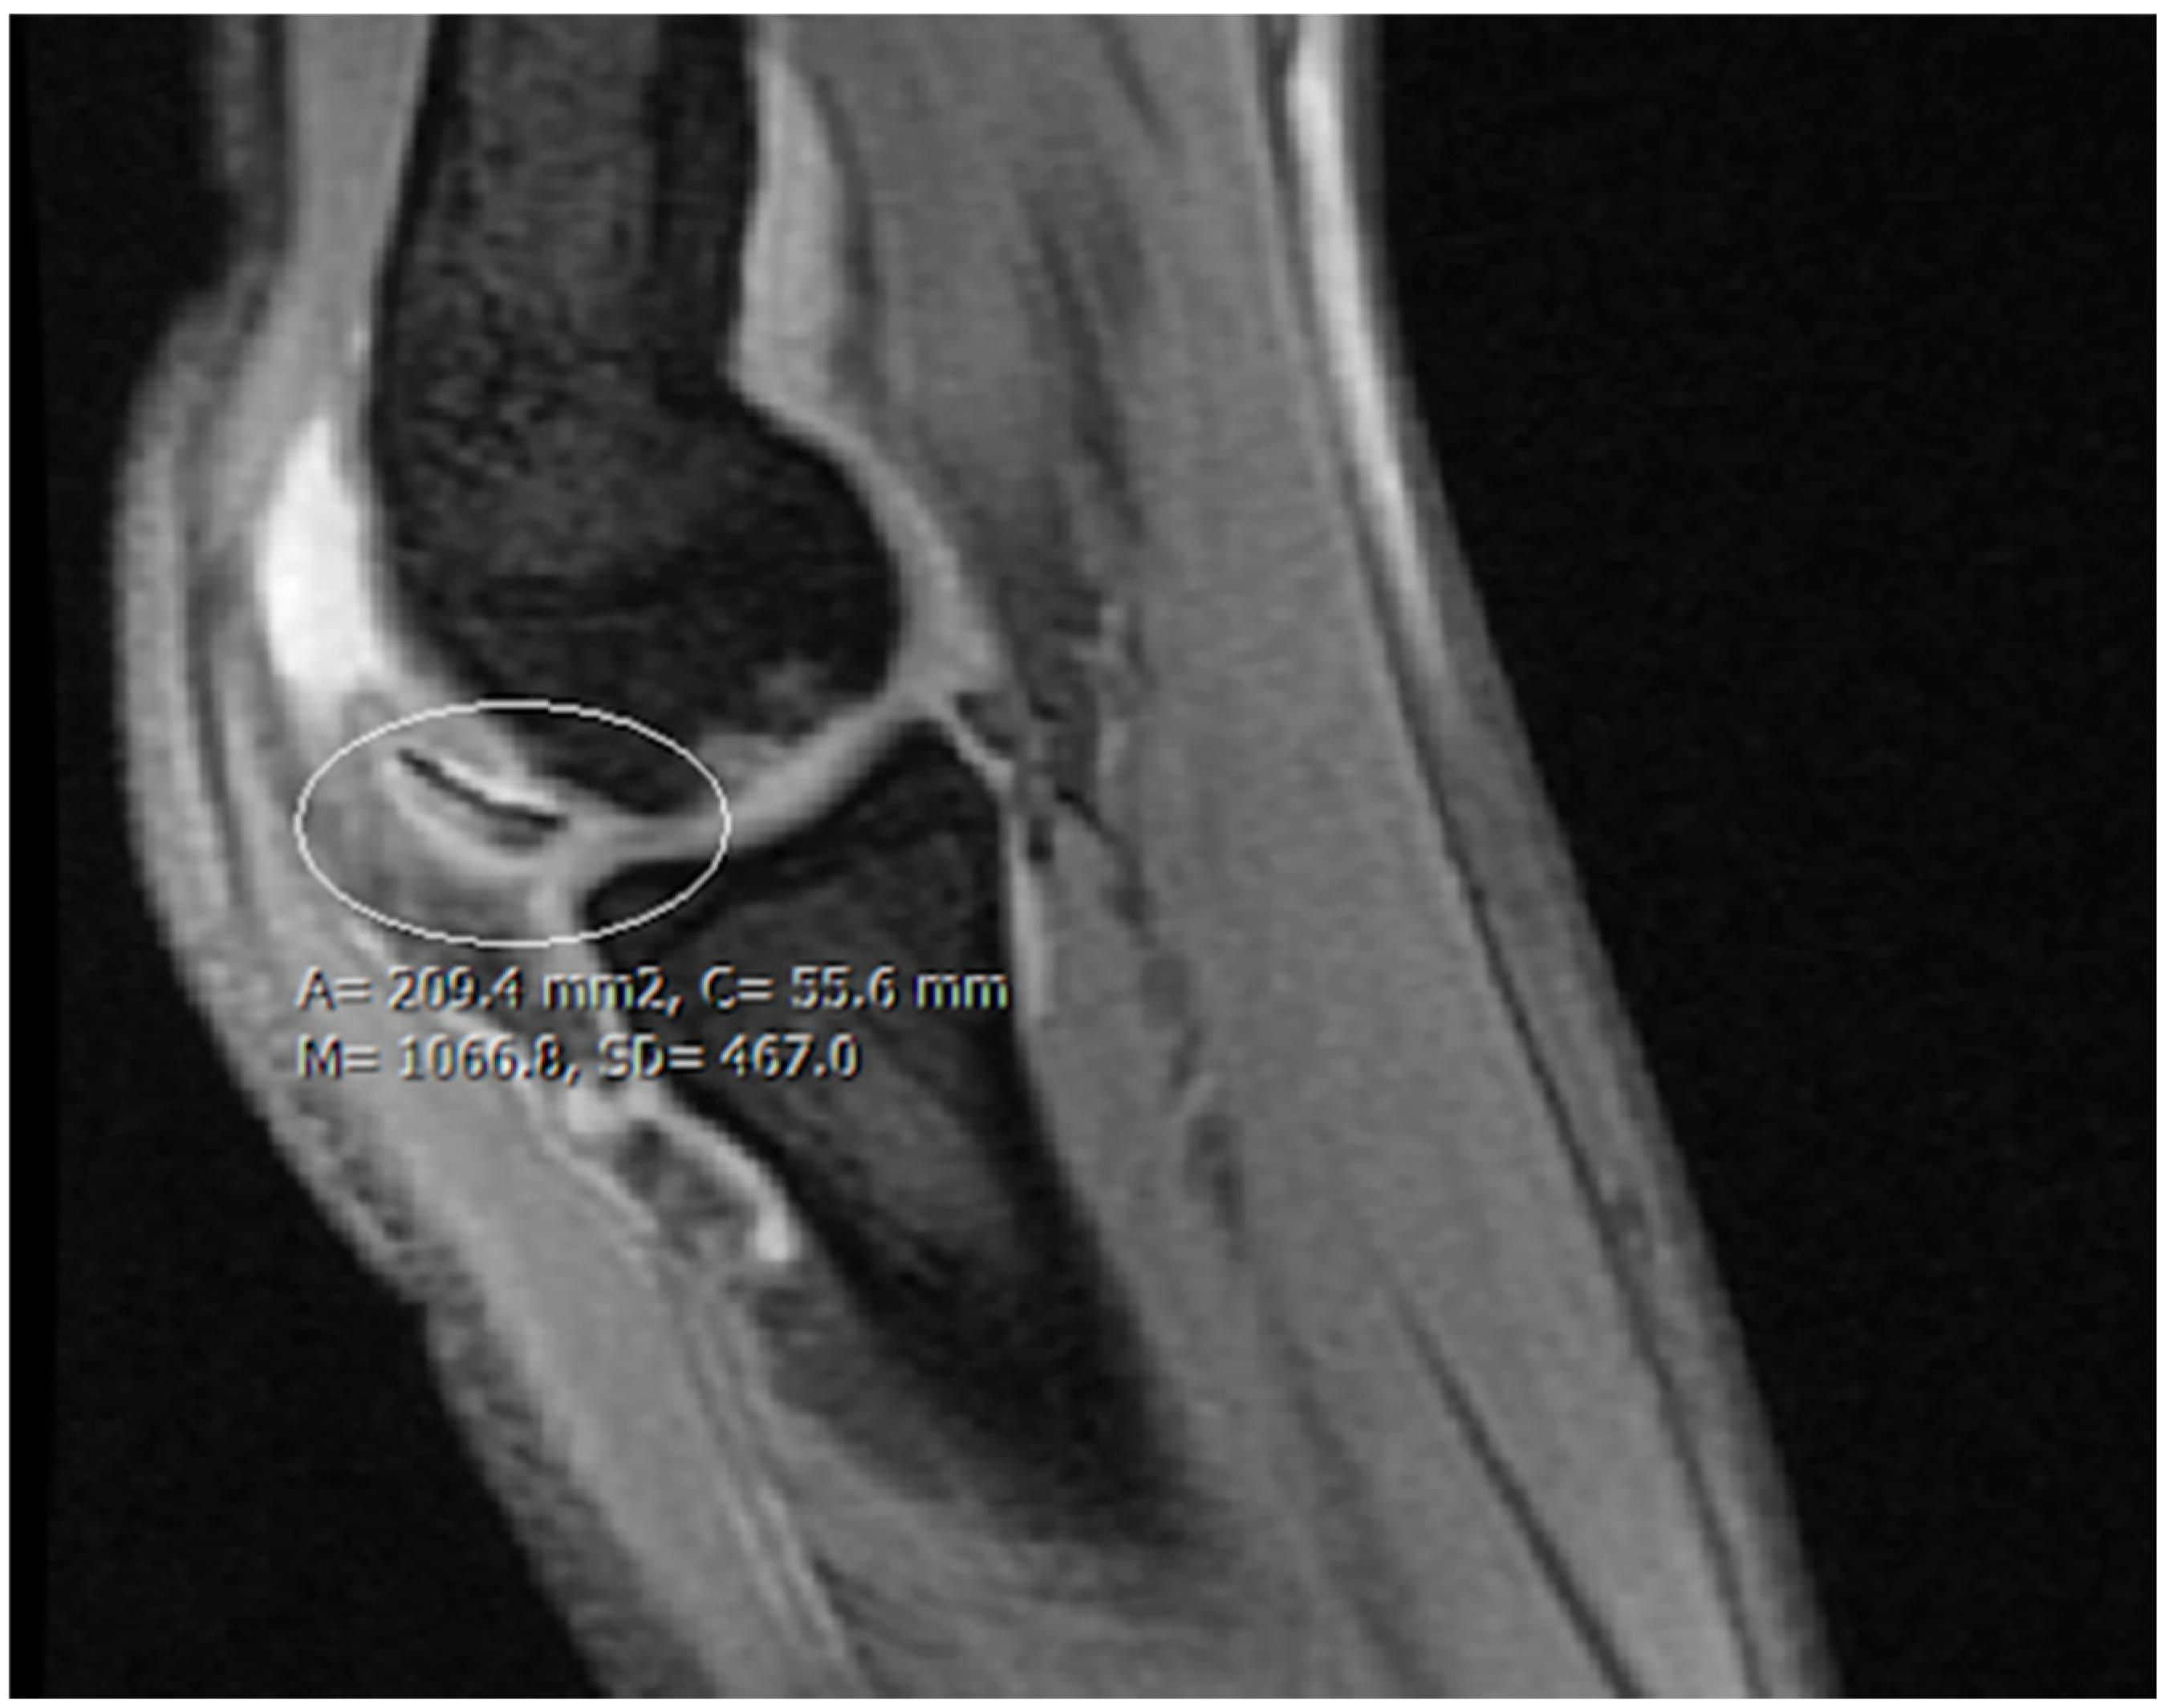

| Stage 2 | Partially detached osteochondral fragment | A lesion with signs of early separation | Lesions with partial discontinuity which are stable when probed | Articular cartilage is breached, with a low signal rim behind the fragment indicating fibrous attachment | Osteochondral fragment with clear margins, without fluid in between | Epiphyseal cartilage lesion with complete or incomplete rim calcification |

| Stage 3 | Completely detached, non-displaced | Partially detached lesion | Lesions with complete discontinuity which are not dislocated (Dead in situ) | High signal changes behind the fragment indicate synovial fluid between the fragment and the underlying subchondral bone | Fluid is partially visible between the fragment and bone | Partially or completely ossified lesion |